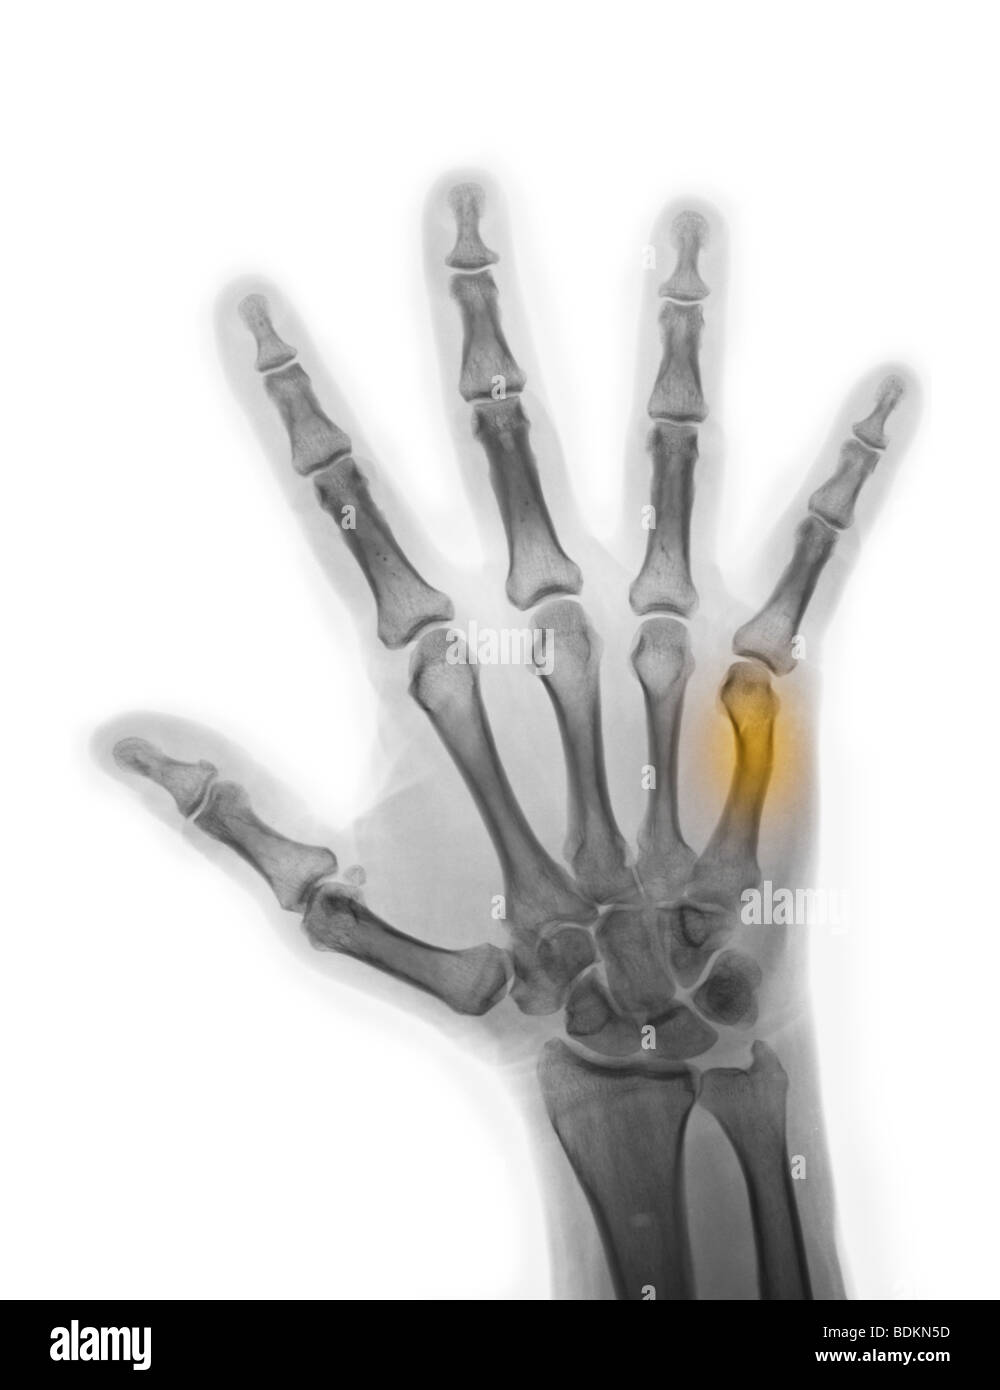

Boxer's Fracture X Ray . Contributed by s bhimji md Fracture of the 4th or 5th metacarpal caused by an axial load, typically from punching a person or object; Boxer’s fracture is the fifth metacarpal neck fracture resulting from direct trauma to the clenched fist. Typical case of boxer's fracture, as a transverse fracture of 5th metacarpal neck. Boxer’s fractures are fractures of the ring or small metacarpal neck that typically occur following an axial impact with a clenched. Pain or swelling along the 4th or 5th metacarpals;. Emergency management of boxer’s fractures.

xray of the hand of a man showing a healing boxer's fracture, a break Boxer's Fracture X Ray Emergency management of boxer’s fractures. Boxer’s fractures are fractures of the ring or small metacarpal neck that typically occur following an axial impact with a clenched. Boxer’s fracture is the fifth metacarpal neck fracture resulting from direct trauma to the clenched fist. Fracture of the 4th or 5th metacarpal caused by an axial load, typically from punching a person or. Boxer's Fracture X Ray.

hand xray showing a healing boxer's fracture Stock Photo Alamy Boxer's Fracture X Ray Boxer’s fracture is the fifth metacarpal neck fracture resulting from direct trauma to the clenched fist. Fracture of the 4th or 5th metacarpal caused by an axial load, typically from punching a person or object; Emergency management of boxer’s fractures. Typical case of boxer's fracture, as a transverse fracture of 5th metacarpal neck. Boxer’s fractures are fractures of the ring. Boxer's Fracture X Ray.

xray showing a healing boxer's fracture in a 56 year old man Stock Boxer's Fracture X Ray Boxer’s fracture is the fifth metacarpal neck fracture resulting from direct trauma to the clenched fist. Contributed by s bhimji md Fracture of the 4th or 5th metacarpal caused by an axial load, typically from punching a person or object; Typical case of boxer's fracture, as a transverse fracture of 5th metacarpal neck. Emergency management of boxer’s fractures. Boxer’s fractures. Boxer's Fracture X Ray.

hand xray of a 57 year old man showing a 5th metacarpal (boxer's Boxer's Fracture X Ray Emergency management of boxer’s fractures. Boxer’s fractures are fractures of the ring or small metacarpal neck that typically occur following an axial impact with a clenched. Contributed by s bhimji md Typical case of boxer's fracture, as a transverse fracture of 5th metacarpal neck. Pain or swelling along the 4th or 5th metacarpals;. Boxer’s fracture is the fifth metacarpal neck. Boxer's Fracture X Ray.